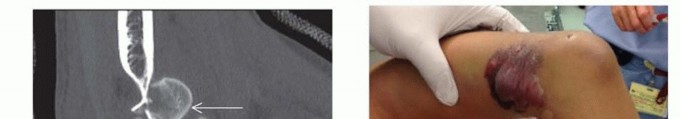

FIG 2 • A,B. A 15-year-old boy with type IIIA open distal humerus comminuted T-condylar humerus fracture. C,D. Three months following open reduction and internal fixation with olecranon osteotomy. Range of motion 0 to 140 degrees with no pain. Older children and young adolescents will often require an open approach. Comminution in the fossa may necessitate an olecranon osteotomy (FIG 2).Generally, pediatric fractures are less comminuted than adult fractures and may not require a full osteotomy.A Morrey slide approach is used in such a case where the triceps and ulnar periosteum are elevated off the ulna medially to expose the distal humerus without performing an osteotomy.3It was originally described to avoid olecranon osteotomies in cases where total elbow replacement would be a salvage operation.It can be useful in adolescents because the fractures are not as comminuted, but excellent visualization of the joint is desirable to provide anatomic reduction and restoration of elbow function. FIG 3 • A. A 13-year-old boy with a T-condylar humerus fracture with coronal split of the capitellum. B.

Open injuries should be addressed surgically within 24 hours; closed injuries may be addressed semielectively.Attention is given to the distal radius; “floating elbows,” in which both the distal humerus and distal radius and/or ulna are affected, are not uncommon. These injuries should be identified early, as they are at increased risk for compartment syndrome.The soft tissue envelope is an important consideration. Fracture blisters (see FIG 3B) can be present, which can compromise the sterility and the closure of the procedure.The vast majority of T-condylar humerus fractures require operative treatment. In younger children, a percutaneous or mini-open approach may be possible.In older children and adolescents, an open posterior approach offers direct visualization and anatomic reduction and fixation of fracture fragments.